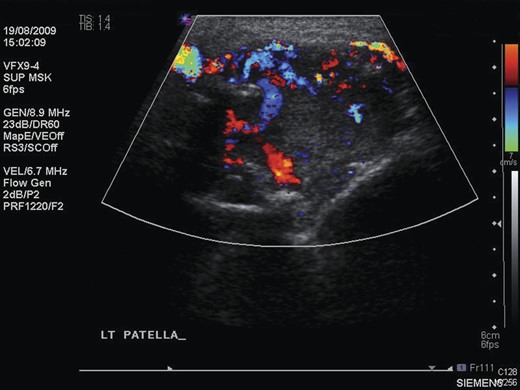

Repeat radiographs performed by his general practitioner 19 months after initial presentation (Figs 4–6) revealed a large lucency within the patella and a discontinuity in the anterior cortex of the inferior pole suggesting pathological fracture. A bone scan was arranged and demonstrated isolated abnormal tracer activity around the left patella (Fig. 7). Due to the pacemaker a computed tomography (CT) scan was performed to further characterize the lesion. This confirmed a large lucent area occupying most of the patella with multiple areas of cortical disruption along its anterior border (Fig. 8). Since the exact nature of the lesion could not be determined an ultrasound-guided biopsy was suggested but ultrasound screening revealed the lesion to be highly vascular (Fig. 9). In view of this the radiologist performed a renal ultrasound, which revealed a large mass arising from the superior pole of the left kidney. Subsequent CT of the chest, abdomen and pelvis followed demonstrating the extent of disease. There was a large (13 × 8.5 × 9 cm) mass arising from the superior pole of the left kidney (Fig. 10), the appearances of which were consistent with a primary RCC. Metastases were found in both adrenals and lungs, but no other bone metastases. Since diagnosis, the patient has had a left nephrectomy and is currently receiving radiotherapy and zolendronic acid treatment for the patella metastasis. At the time of writing this report the patient's patella lesion continues to be managed non-operatively.

Ultrasound scan of the left patella, showing extensive neovascularization and increased flow within the lesion.